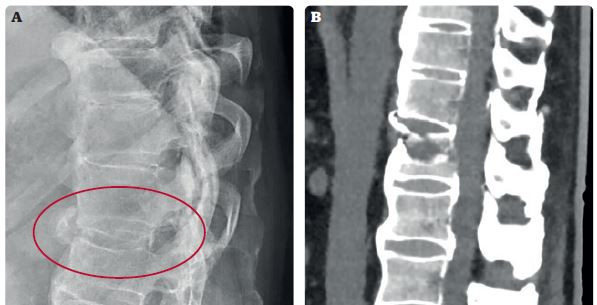

• Při podezření na trauma páteře bychom měli být velmi obezřetní. V případě komprese obratlového těla je nález většinou dobře viditelný i na prostém RTG snímku, vždy bychom však měli zvážit doplnění CT k přesnějšímu posouzení míry kostního traumatu.

• Riziko neodhalení zlomeniny při klasickém RTG vyšetření vzniká především u pacientů s ankylozující spondylitidou nebo Forestierovou chorobou (difuzní idiopatická skeletální hyperostóza), kdy dochází k extenzivní osifikaci předního a případně i zadního podélného vazu páteře. V těchto případech jsou velmi časté tzv. extenční zlomeniny, u kterých je přední páteřní sloupec přetržen zepředu dozadu, což na prostých snímcích není vždy dobře hodnotitelný nález (obr. 3). Jedná se však o velmi nestabilní zlomeniny, které vždy musejí být ošetřeny operačně.

Obr. 3 Snímky extenční zlomeniny obratle L1 u pacienta s difuzní skeletální hyperostózou. Na rtg (A) jsou traumatické změny velmi diskrétní a snadno přehlédnutelné (radiologem nebylo popsáno žádné trauma). CT (B) stejného pacienta s jasně viditelnou lomnou linií v obratli – jedná se o velmi nestabilní poranění, které je nutno operovat.Terapeutický přístup k bolestem zad by měl být individuální, tedy specificky nastavený pro každého pacienta dle získaných anamnestických dat a výsledku klinických a paraklinických vyšetření. Prognóza akutních bolestí zad je velmi dobrá – až u 90 % pacientů je zaznamenáván ústup bolestí do 6–8 týdnů od počátku symptomů. Při perzistenci obtíží po tomto časovém intervalu však již další redukce bolesti není tak výrazná.9